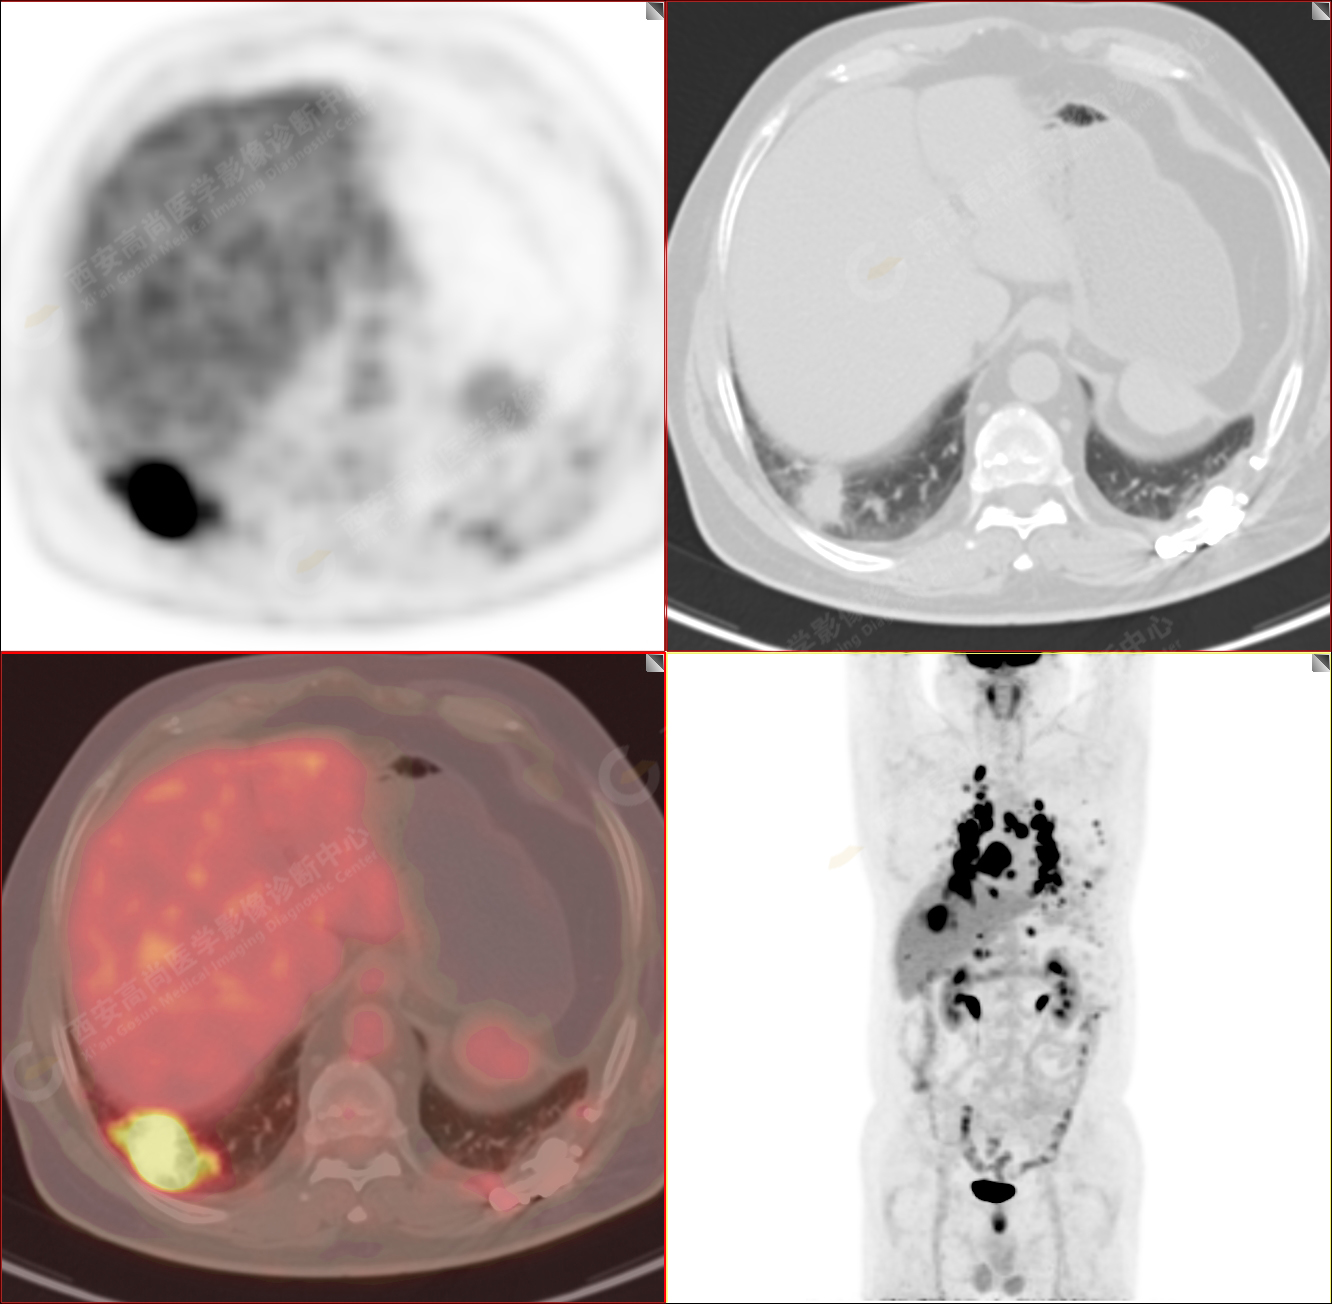

PET/CT-MR診斷結(jié)節(jié)病雙肺及全身多發(fā)淋巴結(jié)廣泛累及1例【西安高尚病例】

男性,53歲,頭暈半月入院,CT發(fā)現(xiàn)肺內(nèi)腫塊,雙肺多發(fā)大小不等實(shí)性及粟粒樣結(jié)節(jié),雙肺門(mén)及縱隔多發(fā)腫大淋巴結(jié)。病程中無(wú)發(fā)熱、胸悶氣及胸部不適。既往:左側(cè)肋骨外傷史。

PET/CT圖像